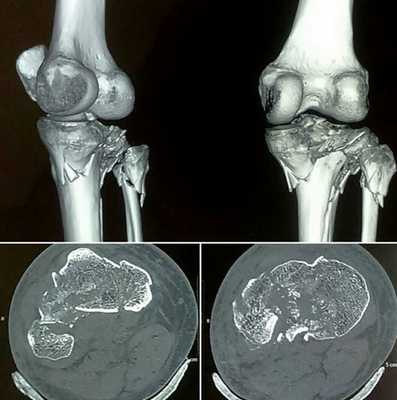

Изменения головки большеберцовой кости на томограмме

Компьютерная томография колена

Остеосаркома бедренной кости на снимке коленного сустава

КТ колена

С помощью компьютерной томографии визуализируют нарушения связочного аппарата, костных суставных поверхностей, гиалинового хряща, синовиальной оболочки и капсулы сочленения. Ограничение подвижности и боль возникают чаще при травмах, воспалительных и дегенеративных патологиях.

КТ коленного сустава позволяет диагностировать хондромаляции (разрушение хряща), повреждения менисков, разрывы крестообразных связок. В результате контрастной процедуры выявляют онкологические процессы, заболевания сосудов, липоартрит и пр.